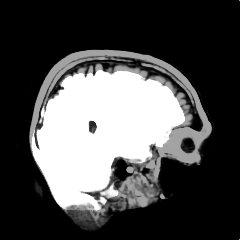

We introduce a neural network framework, utilizing adversarial learning to partition an image into two cuts, with one cut falling into a reference distribution provided by the user. This concept tackles the task of unsupervised anomaly segmentation, which has attracted increasing attention in recent years due to their broad applications in tasks with unlabelled data. This Adversarial-based Selective Cutting network (ASC-Net) bridges the two domains of cluster-based deep learning methods and adversarial-based anomaly/novelty detection algorithms. We evaluate this unsupervised learning model on BraTS brain tumor segmentation, LiTS liver lesion segmentation, and MS-SEG2015 segmentation tasks. Compared to existing methods like the AnoGAN family, our model demonstrates tremendous performance gains in unsupervised anomaly segmentation tasks. Although there is still room to further improve performance compared to supervised learning algorithms, the promising experimental results shed light on building an unsupervised learning algorithm using user-defined knowledge.